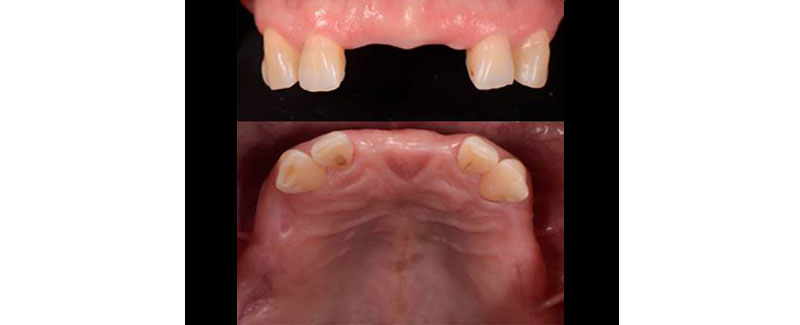

A relative symmetry of remaining teeth may provide functional and biomechanical advantages that make keeping these teeth worth considering. Also, the strategic position within the arch could make a compelling argument for keeping them. In other words, if there are sound vital intact canines or sound intact canines and molars, it would definitely be worth considering keeping them. (Fig. 4)